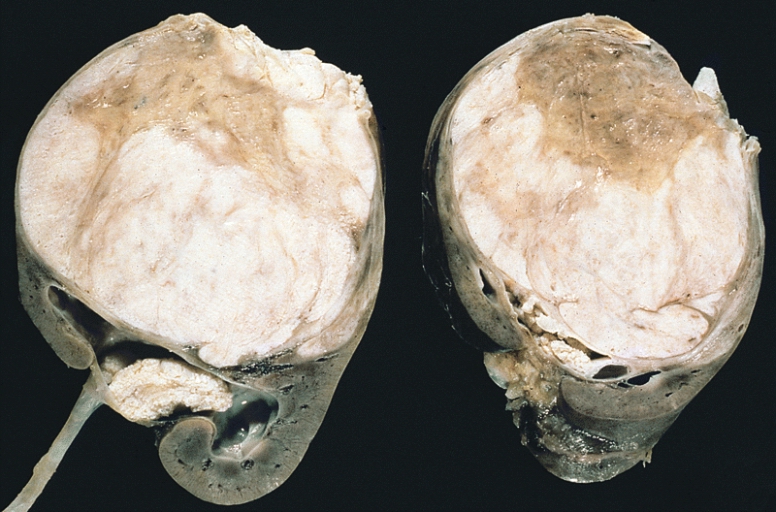

Wilms Tumor

Wilms tumor is a malignant kidney tumor composed of primitive glomeruli, tubules, and stromal cells blastema which is an immature kidney mesenchyme.

The average age of a child who develops a Wilms tumor is 3-years-old.

Symptoms of Wilms tumor include:

- Large mass

- Unilateral flank mass

- Hematuria

- Hypertension brought on by renin secretion

Wilms tumor is associated with WT1 mutation, especially in syndromic cases.